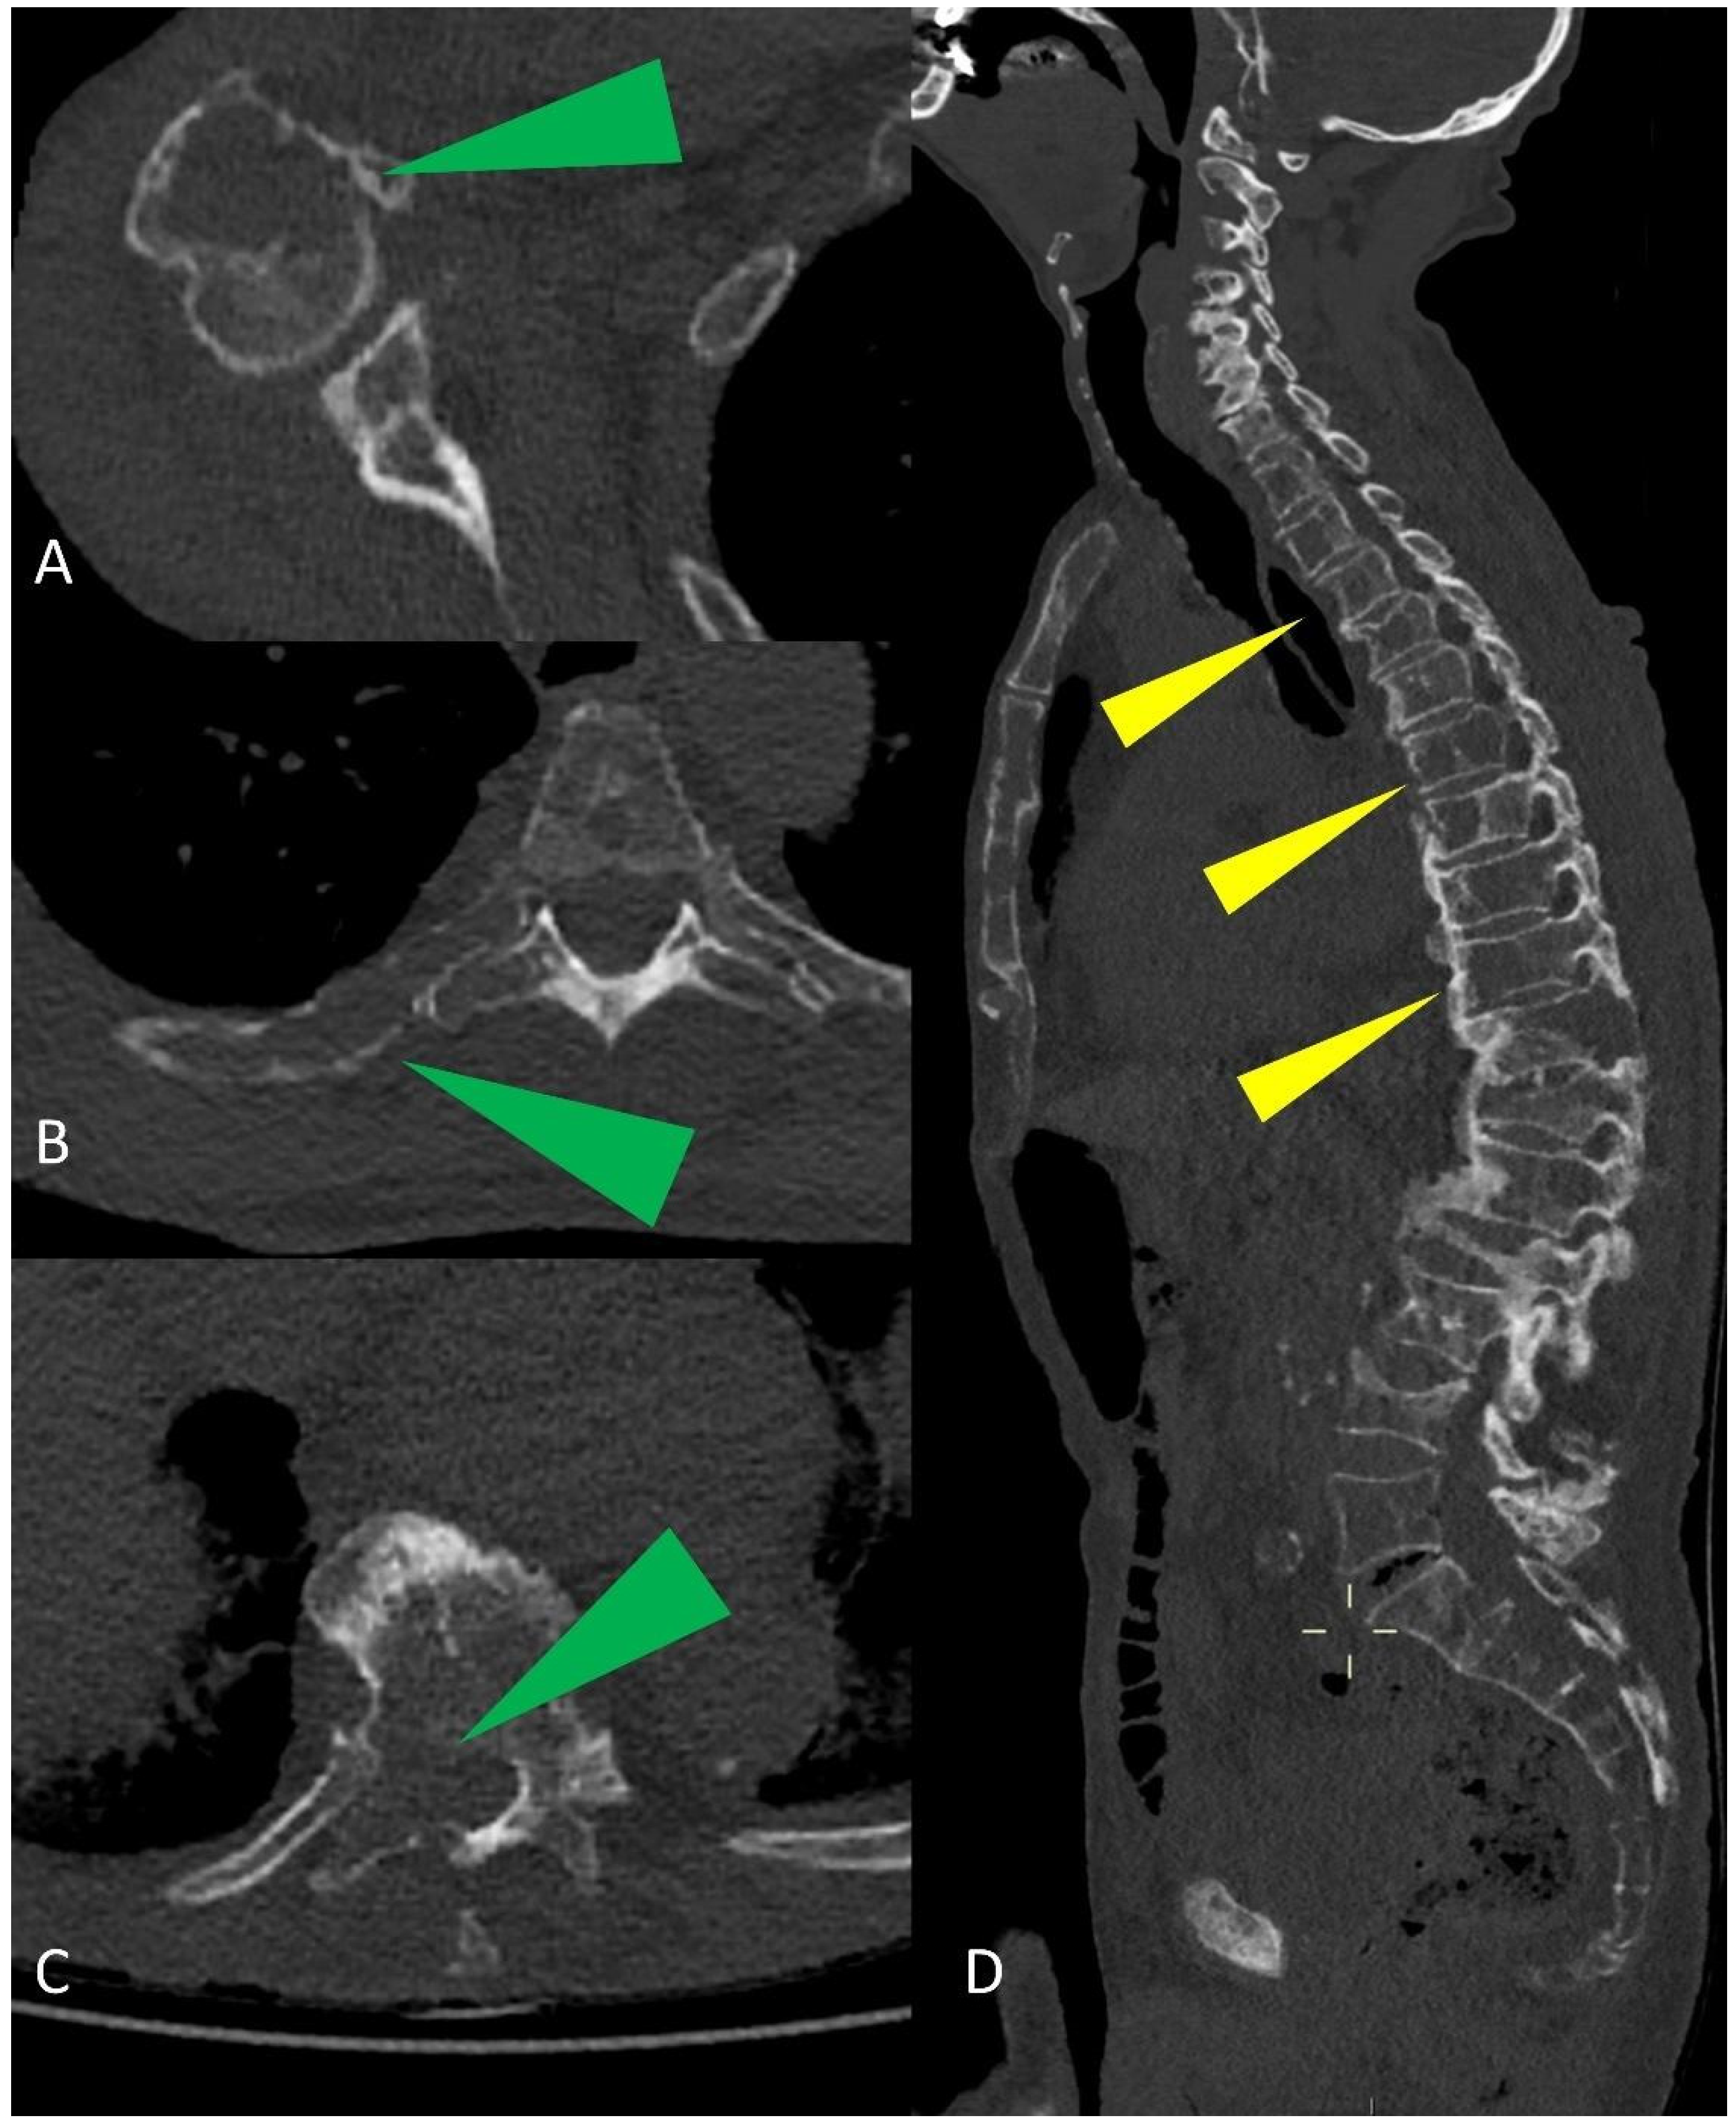

Figure 5.

Multiplanar CT images showing humeral, ribs, and vertebral osteolytic lesions (green arrowheads in (A–C)); multiple osteolytic lesions of the spine (yellow arrowheads in (D)).